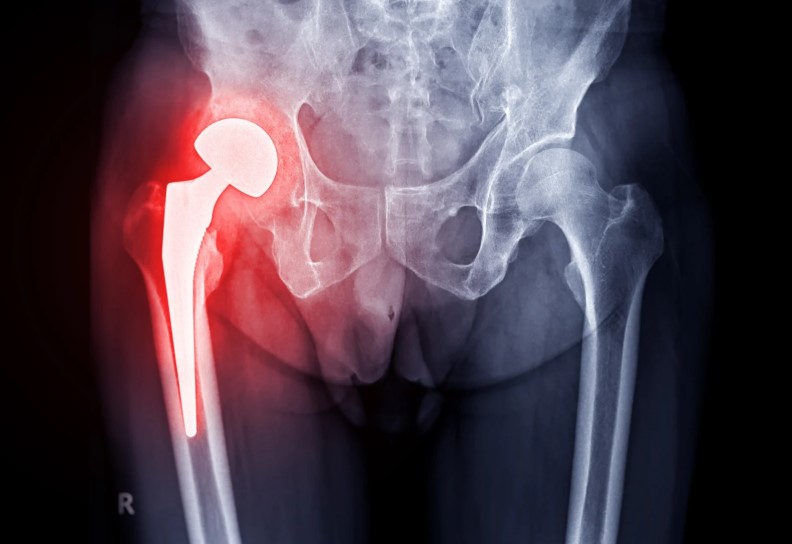

The Direct Anterior Approach (DAA) hip replacement is a revolutionary surgical method designed to minimize tissue trauma and speed up recovery. Unlike traditional hip replacement techniques that require cutting through muscles, the DAA approach allows access to the hip joint through a natural muscle plane. This means less pain, faster rehabilitation, and better post-surgical stability. At Tec Orthopedics, Dr. Tec performs this advanced procedure with exceptional precision, using modern instruments and evidence-based techniques to ensure a smooth recovery and long-term results. The goal is to help patients return to walking, driving, and enjoying daily life without restriction.

Patients today seek outcomes that go beyond pain relief—they want a faster return to independence and improved long-term function. The Direct Anterior Approach delivers exactly that. Because it spares major muscles, patients experience less post-operative pain, shorter hospital stays, and an earlier return to walking. The technique also enables more accurate implant placement, improving hip stability and longevity. At Tec Orthopedics, this approach represents the perfect blend of innovation and compassion. Every hip replacement performed is guided by the goal of minimizing discomfort and maximizing confidence in movement. Patients often report feeling steadier on their feet and more active sooner compared to traditional methods.

The Direct Anterior Approach is ideal for patients who experience persistent hip pain or stiffness that no longer responds to medication, therapy, or injections. Those diagnosed with advanced arthritis, degenerative joint disease, or avascular necrosis are prime candidates for this form of hip replacement. Active adults and seniors alike can benefit from its muscle-sparing advantages, especially those who wish to resume daily activities and hobbies sooner. Tec Orthopedics has helped countless patients—from professionals to retirees—regain their independence and confidence through this modern, minimally invasive solution.